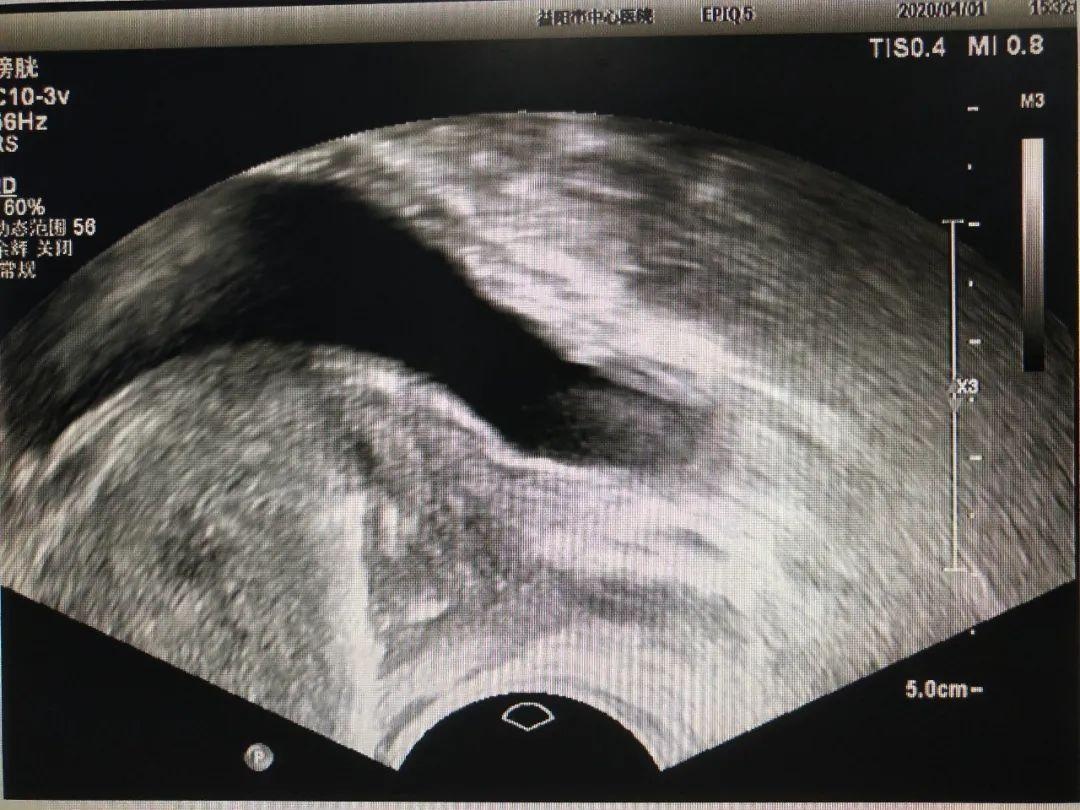

3、 经直肠超声引导下前列腺活检术诊断前列腺病变。

图2 前列腺活检